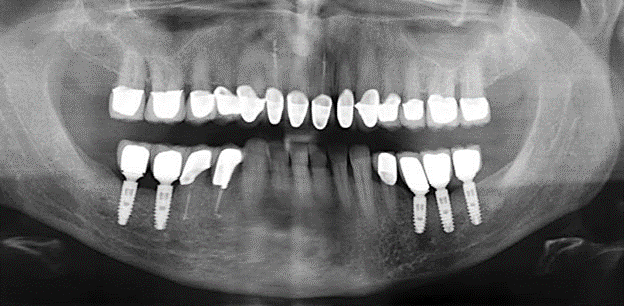

Fig. 1: Panoramic radiograph of initial situation in 2004.

A 52-year-old patient presented in our clinic for the first time in 2004 following tooth loss in the third quadrant, expressing a desire for a new prosthetic restoration. Periodontal and radiological diagnostics revealed the need for extensive periodontological treatment. In addition, teeth 48, 28 and 27 were attributed a very poor prognosis and were subsequently extracted (Fig. 1). Following the successfully completed, systematic periodontological treatment, a fixed dental implant was inserted with the introduction of five implants in tooth regions 35, 36, 37, 46 and 47. Prosthetic treatment of the natural teeth was effected with veneered zirconium dioxide ceramic crowns; the implants were composed of two-piece, individual zirconium dioxide abutments and similarly veneered crowns made of a zirconium dioxide ceramic (Cercon base colored, Dentsply Sirona Lab). Definitive insertion of the prosthetic restoration occurred in 2005.

The ten-year check-up revealed no indications of advancing clinical attachment loss or peri-implant bone substance loss (Fig. 3).